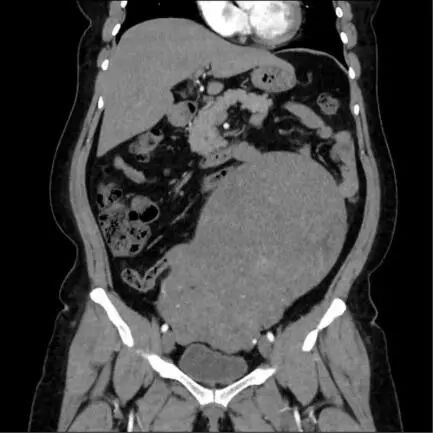

患者李女士(化名)2015年因子宫肌瘤在外院接受了腹腔镜子宫肌瘤剔除术,她觉得手术后恢复得很好,没有坚持定期检查。最近因胃受轻微撞击,出现持续性胃痛,到潜江市中心医院就诊。超声波检查显示,她的子宫形状异常,增大至怀孕第七个月大小,肌壁间可见大量大小不一的肌瘤样间隙。最大的在e的横截面约为110mm×90mm。由于患者肥胖,之前并未注意到腹部异常。根据超声结果,门诊医生建议尽快住院手术。

由于肿瘤体积较大,生长速度不确定,且患者有肌瘤手术史,为了排除子宫肉瘤等恶性病变的可能性,妇科主任周军对此高度重视,迅速启动多学科会诊机制。根据影像学特点和临床指征进行综合评估,制定个体化手术方案和急诊方案,确保安全、全面的诊疗过程。